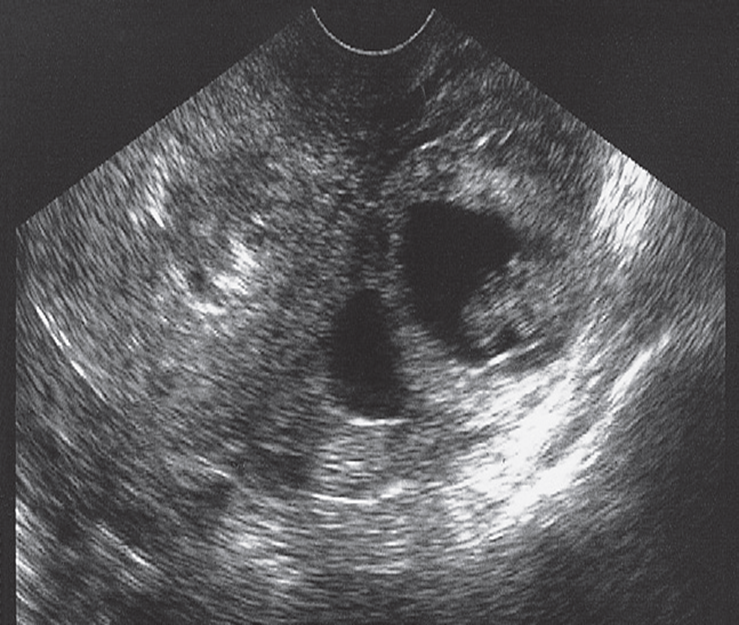

Ectopic pregnancy.

Transvaginal scan in a patient whose pregnancy test was positive. The uterus is seen containing no gestational sac and there is a predominantly cystic adnexal mass containing a fetal echo surrounded by amniotic fluid.